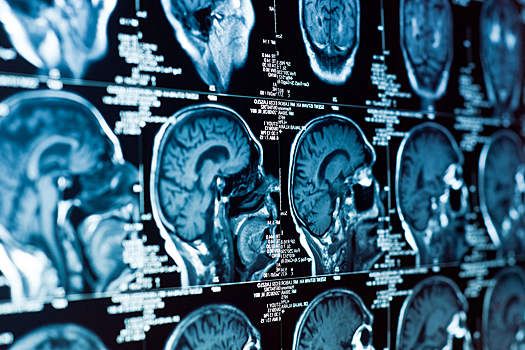

Сейчас ученые изучают структуры мозга у 140 добровольцев с помощью продвинутой нейровизуализации и параллельно тестируют первые прототипы устройств, усиливающих работу лимфатических сосудов. Авторы подчеркивают, что такая стратегия может стать альтернативой существующим методам, которые требуют экстренной доставки пациента в больницу и могут нести риск кровотечений.